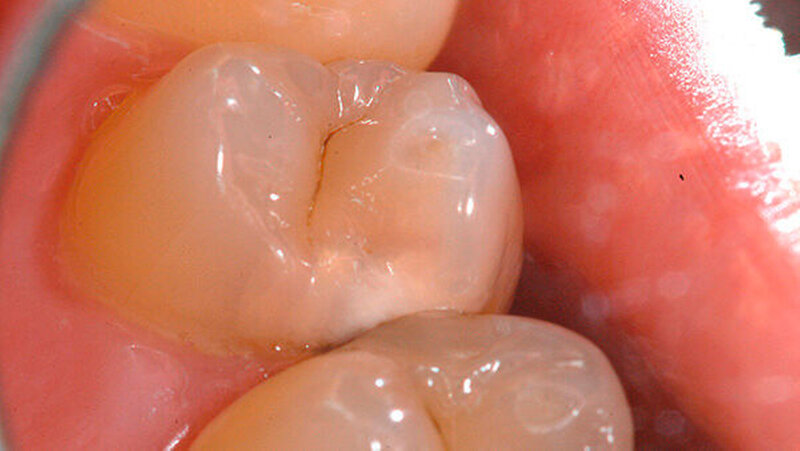

Ein 43-jähriger Patient stellte sich zur Routinekontrolle in der Poliklinik für Zahnerhaltung des Universitätsklinikums Münster vor. Die allgemeinmedizinische Untersuchung zeigte keine Besonderheiten. Sowohl der klinische zahnmedizinische Befund als auch die angefertigte Röntgenaufnahme deuteten auf eine Approximalkaries distal an Zahn 14 hin (Abbildungen 1 und 2). Daher wurde der Patient auf die Notwendigkeit einer Füllungstherapie hingewiesen.